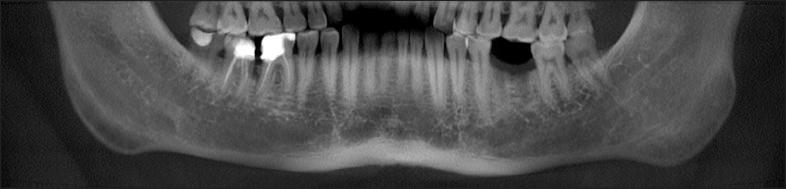

The purpose of present article was to review the classifications suggested for assessment of the jawbone anatomy, to evaluate the diagnostic possibilities of mandibular canal identification and risk of inferior alveolar nerve injury, aesthetic considerations in aesthetic zone, as well as to suggest new classification system of the jawbone anatomy in endosseous dental implant treatment.

In total 109 literature sources were obtained and reviewed. The classifications suggested for assessment of the jawbone anatomy, diagnostic possibilities of mandibular canal identification and risk of inferior alveolar nerve injury, aesthetic considerations in aesthetic zone were discussed. New classification system of the jawbone anatomy in endosseous dental implant treatment based on anatomical and radiologic findings and literature review results was suggested.

The classification system proposed here based on anatomical and radiological jawbone quantity and quality evaluation is a helpful tool for planning of treatment strategy and collaboration among specialists. Further clinical studies should be conducted for new classification validation and reliability evaluation.